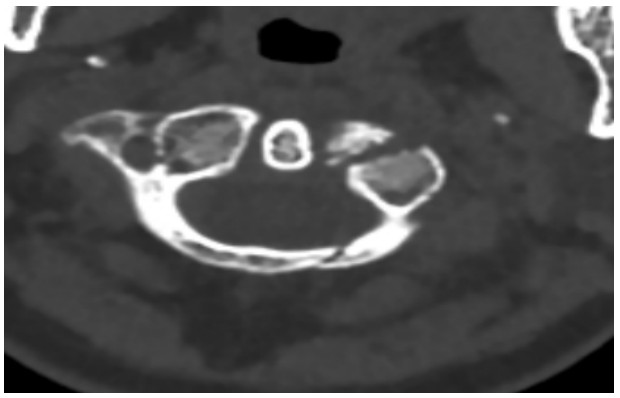

國慶節(jié)前一天,譚女士不幸被門框砸傷頸部,劇烈的疼痛和頸椎的活動受限讓她的世界瞬間陷入了黑暗。在經(jīng)歷了初步的檢查后,譚女士被診斷為寰椎骨折,這個(gè)診斷如同一道晴天霹靂,讓她和家人的心沉入了谷底。絕望中,譚女士被緊急轉(zhuǎn)至衡陽市中心醫(yī)院骨科一區(qū)(脊柱外科),錢軍博士及其團(tuán)隊(duì)在接到這一緊急病例后迅速接診,經(jīng)過細(xì)致的病史詢問、體格檢查和影像學(xué)資料分析,確診譚女士的寰椎骨折伴有寰樞椎體不穩(wěn)定,迫切需要手術(shù)治療以恢復(fù)其穩(wěn)定性??紤]到上頸椎手術(shù)的高風(fēng)險(xiǎn)性,特別是寰樞椎周圍結(jié)構(gòu)復(fù)雜,緊鄰椎動脈和脊髓,手術(shù)過程中的任何微小失誤都可能導(dǎo)致災(zāi)難性后果,錢軍博士團(tuán)隊(duì)頂著壓力,迎難而上,沒有絲毫猶豫,立即行急診手術(shù),投入到緊張的救治工作中。